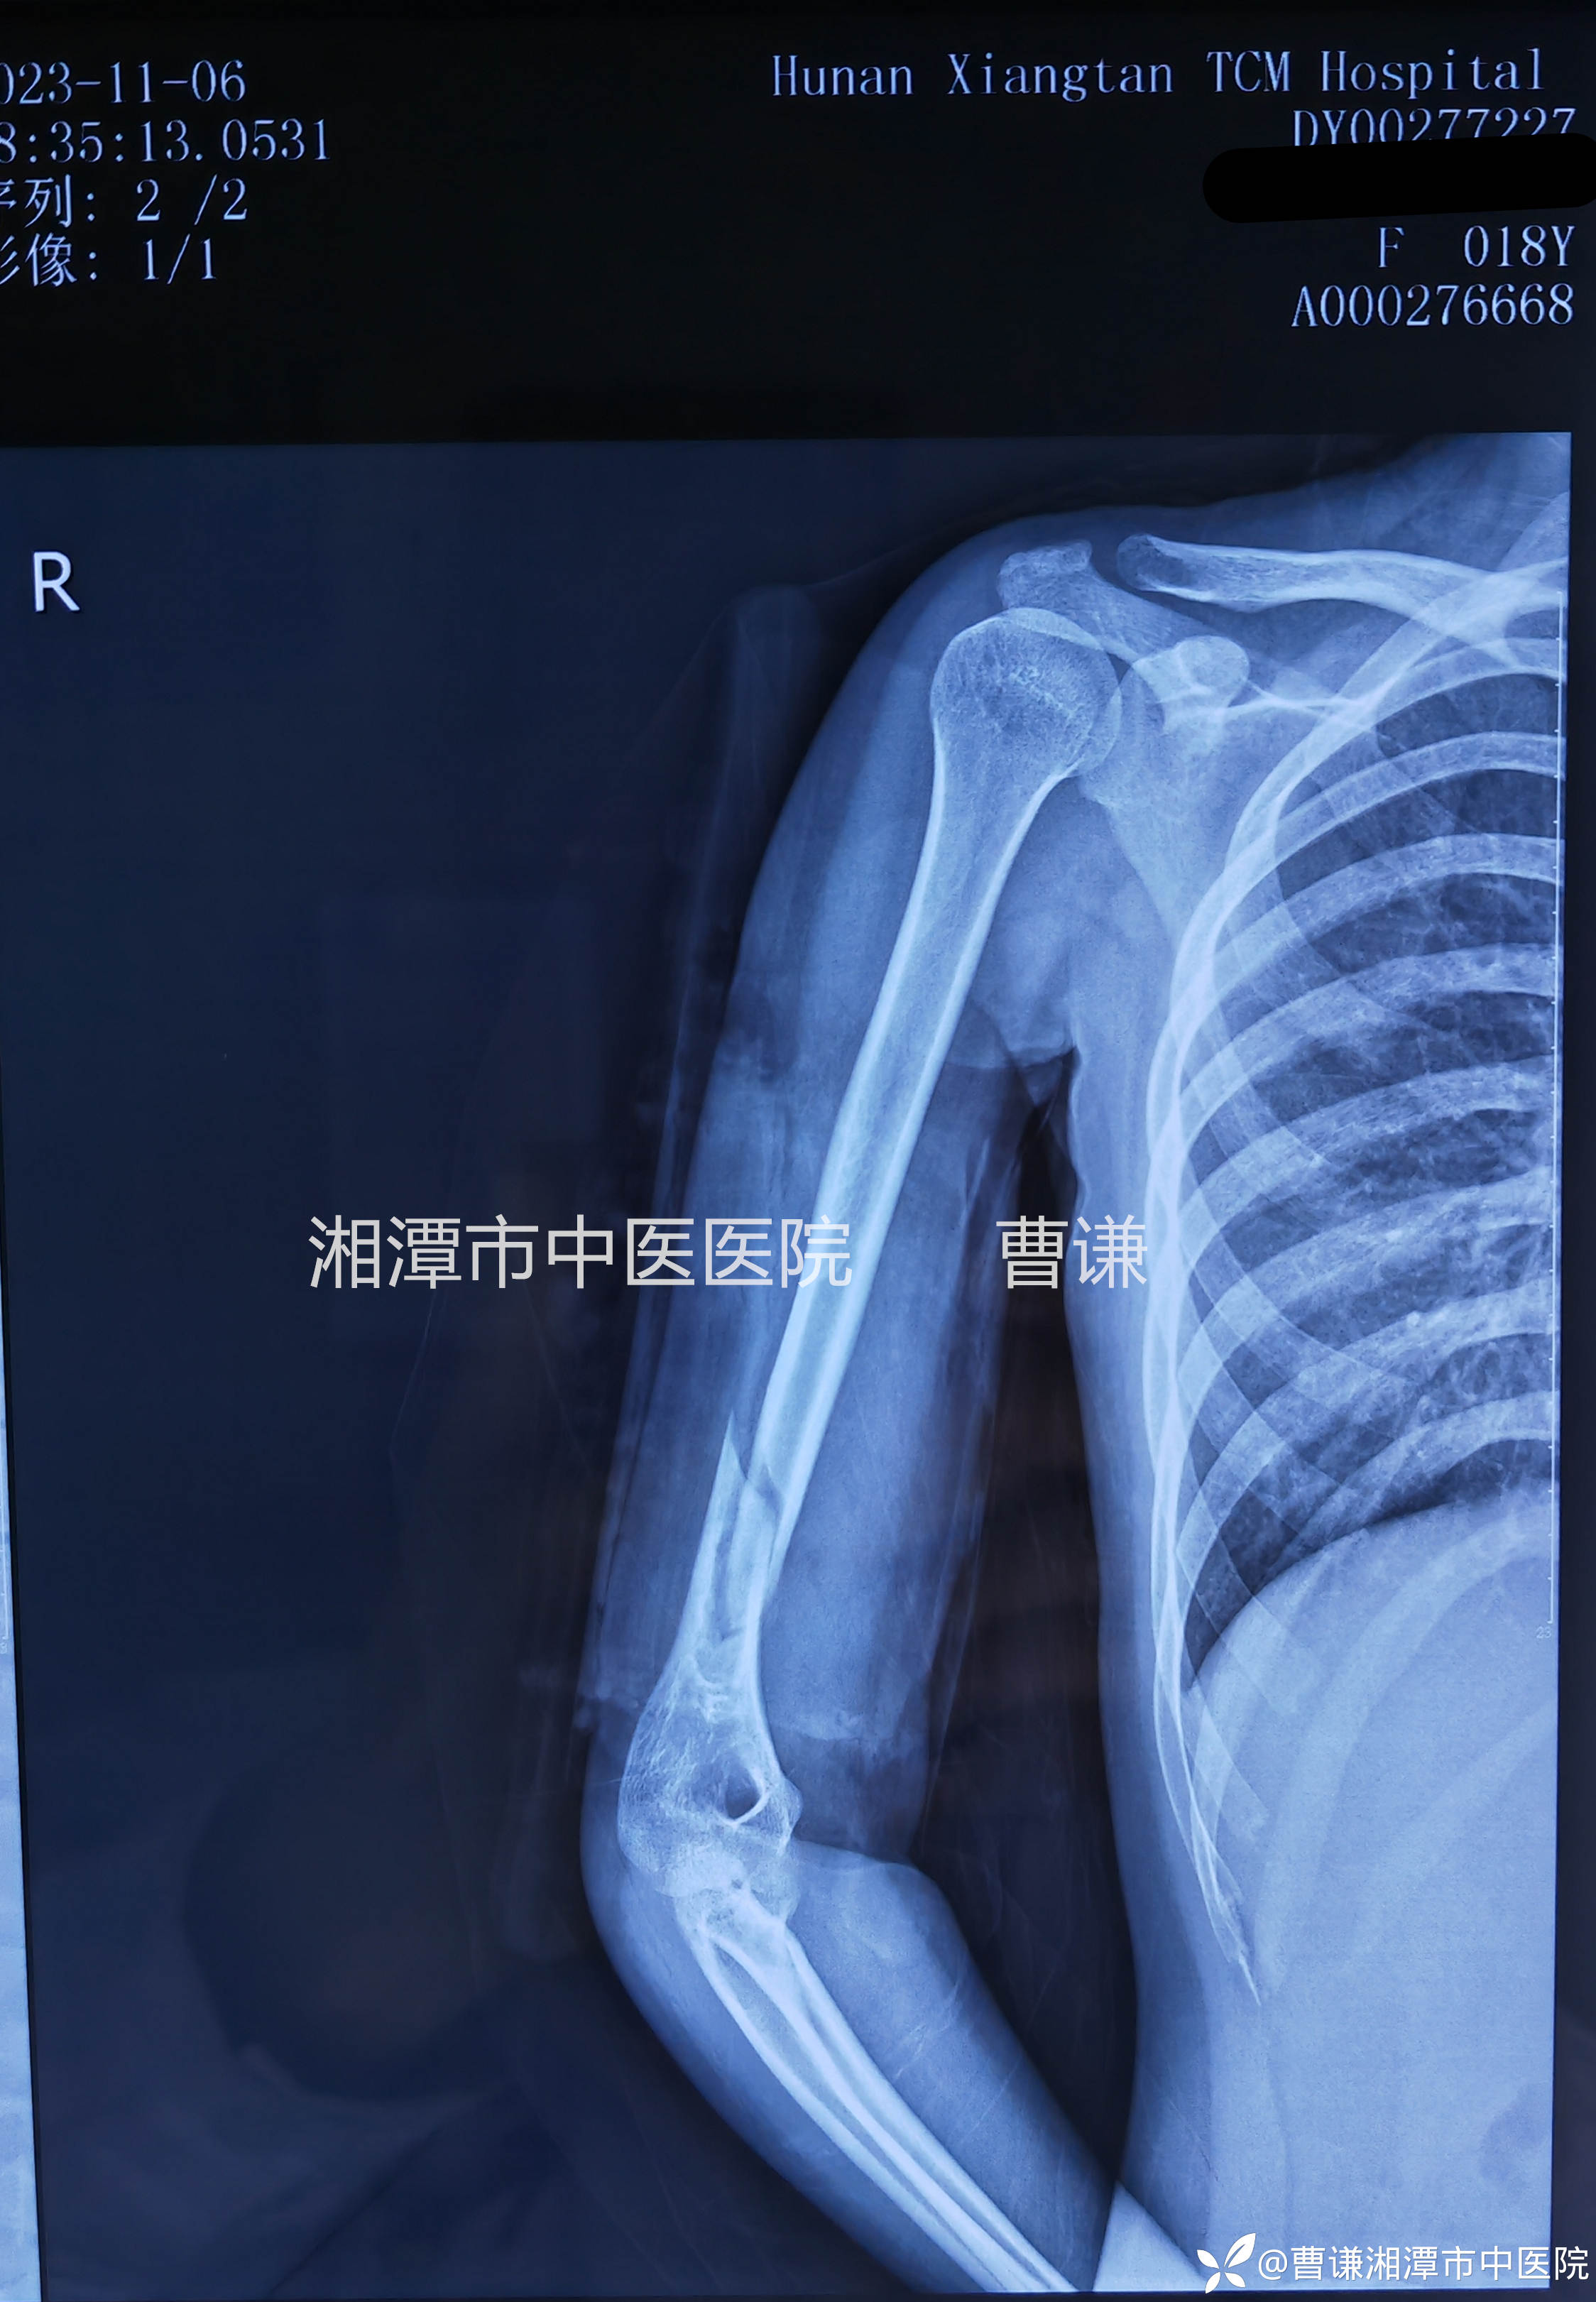

伤后一个半月过来复诊拍片示骨折端见少量骨痂生长,功能基本恢复正常,体查局部无压痛及纵轴叩痛,无畸形及异常活动,拆除外固定,嘱回当地继续功能锻炼。